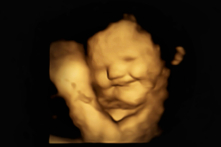

Em bé mỉm cười khi mẹ ăn cà rốt nhưng lại khóc vì hương vị của rau cải xoăn